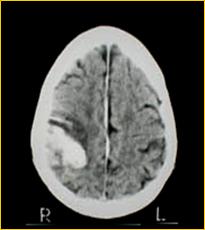

Le patologie che possono portare alla morte cerebrale sono l'emorragia cerebrale da rottura di un vaso intracranico, i traumi cranici ( incidenti stradali, ferite da proiettile ), le neoplasie cerebrali primitive.

EMATOMA SUBDURALE FERITA DA PROIETTILE

REPERTO ANATOMICO DI MASSIVA EMORRAGIA CEREBRALE